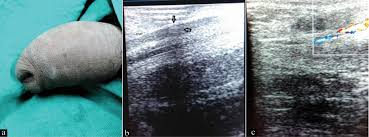

Patients usually present with a smooth cord-like induration on the dorsal penile shaft 1-7 days after prolonged or intensive sexual intercourse but other presentations of disease and triggers for endothelial damage are possible.

Several treatment modalities have been proposed varying from no treatment at all to stripping of the thrombosed vein. The first good news is that it is not an STD sexually transmitted disease like genital herpes and genital warts. Currently treatment is palliative for most patients. Anticoagulation with aspirin heparin or other antiplatelet agents will not expedite healing and is not necessary to prevent additional thrombosis. Treatment and cure for Penile thrombosis Diagnosis of Penile thrombosis Treatment and cure for secondary thrombosis. Pearly Penile Papules or PPP is basically a skin disorder. No other etiological medications drugs or constricting devices were implicated. Thrombectomy and resection of the superficial penile vein are applied surgically in the patients refractory to the medical treatment. The second good news that you can easily heal it with home based remedies.